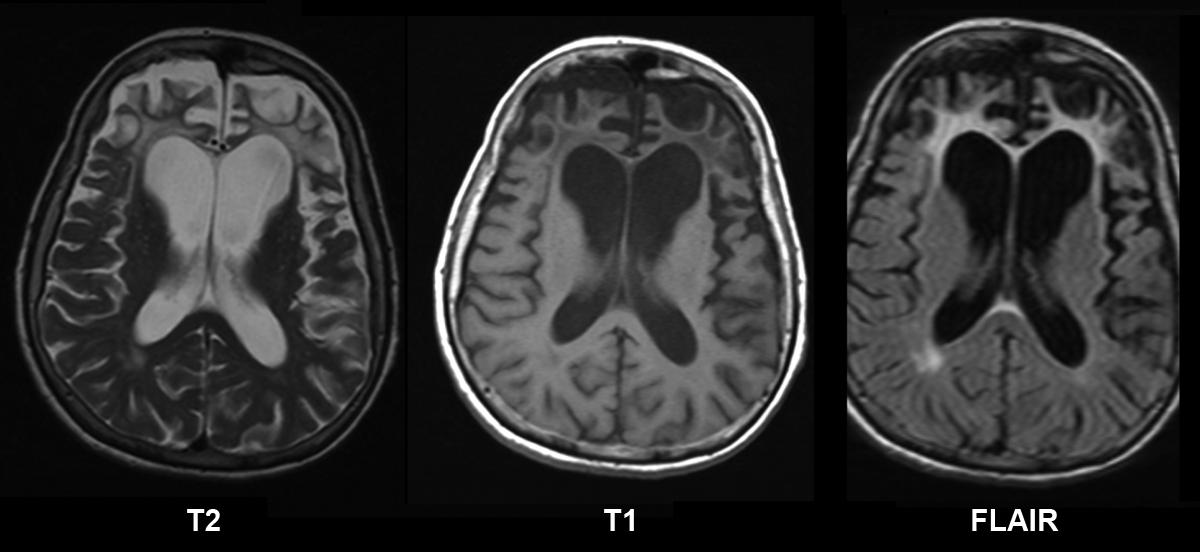

Pick’s disease is a rare type of dementia. It is the disease of parts of brain that control emotions, personality, behavior, and language. Pick’s disease is also referred to as Frontotemporal Dementia or Frontotemporal Lobar Degeneration. In Pick’s disease, the tau proteins clump together to form Pick bodies. Since tau proteins are associated with transportation of nutrients, the disrupted function results in irreversible brain damage due to deranged tau protein’s function. The individual with Pick’s disease exhibits following features: - Aggressive behavior - Excessively vigilant - Uninterested in daily activities - Easily irritable - Mood swings - Impulsive decision-making - Inability to perform unplanned activities - Repetitive actions - Inappropriate language and actions People with Pick’s disease also have issues such as: - Uncoordinated movement - Loss of memory - Stiff or flaccid muscles - Difficulty in movement There is not treatment of Pick’s disease. The management aims at symptomatic relief. Once started, the condition worsens with time. Reference: https://www.webmd.com/alzheimers/guide/picks-disease Image via: https://en.wikipedia.org/wiki/Frontotemporal_dementia